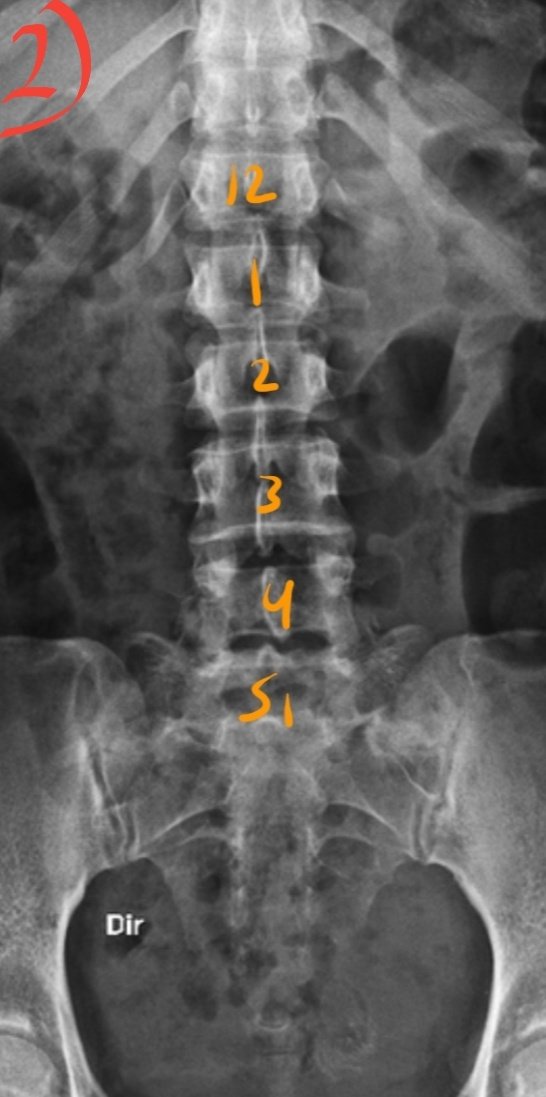

☆٥الفحص الأمامي للفقرات القطنية

AP view of Lumbar spine

معلومات/

•الفقرات القطنية عددها ٥ فقرات.

•أهم فقرة هي القطنية رقم ٣ ،لأنه يتم استخدامها كمركز للشعاع.

•يتم الاستدلال على موقعها بأنها تقع على مستوى حافة الأضلاع السفلى.

Lower costal margin

عدد الفقرات القطنية قد يختلف (مجازاً) عند بعض الأشخاص.

زيادتها إلى ٦ نتيجة عدم إلتحام العجزية الأولى بالثانية (s1-s2) فتظهر كأنها

٦فقرات قطنية

تسمى :

1.Lumbarisation

نقصانها إلى ٤ نتيجة إلتحام القطنية الخامسة بالعجزية الأولى فتظهر كأنه

٤فقرات قطنية

تسمى:

2.Sacralisation

الوضع:

المريض مستلقي على ظهره.

¤وضع prone أفضل للنساء لأنه يوفر حمايةإشعاعيةللمبايض بنسبة 25%-30%¤

•نتأكد أن الحوض غير ملتف أو مائل عن طريق ضبطه بالطلب من المريض أن يسترخي ثم نقوم بالإمساك بمنطقة أعلى الوركين ونرفعه عن الطاولة ثم إفلاته.

•ثني الركبتين وملامسة القدمين للطاولة.

الفائدة من ثني الركبتين وجعل القدمين تلامس الطاولة تقليل (الإنحناء) في الفقرات القطنية

(lordosis)

و حتى يصبح الدسك بين الفقرات موازي للشعاع.

التنفس/

يقوم بإخراج الهواء وايقاف التنفس.

السنتر CR/

L3

●تقييم الفلم/

نعرف عدم وجود إلتفاف

أنspinous process

في منتصف الفقرات✔